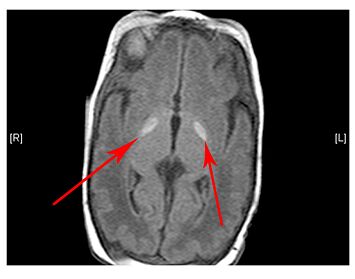

- Lesions (damage) to certain areas of the brain – symmetrical lesions to the area known as basal ganglia is common

(Left) MRI scan of a healthy brain. (Right) The basal ganglia region of the brain shows abnormal signals.